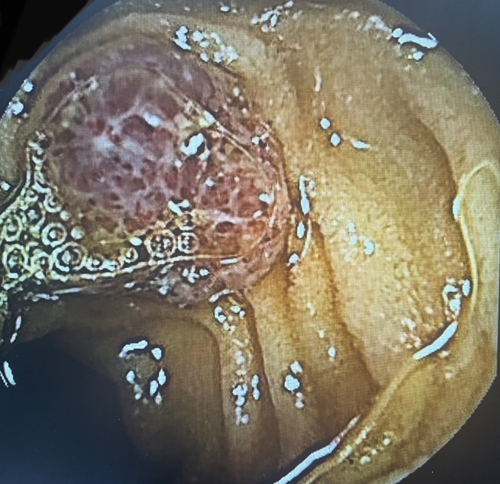

為了進一步查找病因,兒童消化內(nèi)科醫(yī)生決定利用“胃鏡+結(jié)腸鏡+膠囊內(nèi)鏡”三鏡聯(lián)合的方式進行檢查。檢查結(jié)果觸目驚心!

浩浩的胃、小腸及結(jié)腸內(nèi)有多發(fā)藍色大皰樣隆起,大大小小的有20多個,就好像在胃腸內(nèi)灑落了許多藍莓。尤其是小腸病變尤其明顯,最大顆幾乎堵塞了腸腔的一半。

兒童消化內(nèi)科急請血管瘤診療??茖<視\,結(jié)合既往病史,最終診斷為“藍色橡皮皰痣綜合征”。這些藍色大皰樣隆起其實是消化道靜脈瘤,間斷有靜脈瘤破裂出血,浩浩的重度貧血正是由于本病引起的長期消化道慢性出血所致。至此,困擾浩浩一家長達2年之久的反復(fù)貧血之謎得以解開。